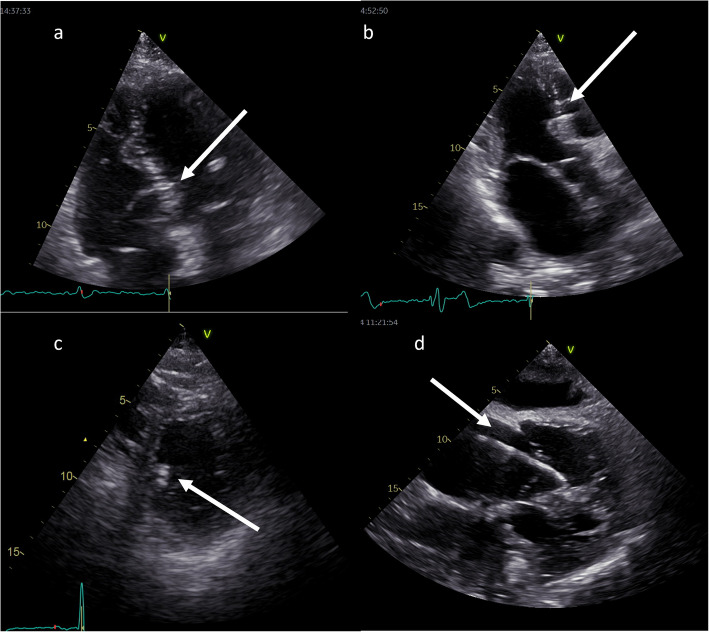

Conduction system pacing (CSP), encompassing His-bundle pacing (HBP) and left bundle branch area pacing (LBBAP), revolutionizes cardiac pacing, allowing a more physiological left ventricular activation than conventional right ventricular (RV) pacing through electrode placed in RV apex, interventricular septum or right ventricular outflow tract. Echocardiography plays a pivotal role in patient assessment, primarily by measuring left ventricular ejection fraction (LVEF) to determine the pacing strategy in alignment with current guidelines. Clinical data, simulations and ongoing trials on CSP explore CSP viability across various LVEF conditions. CSP is supposed to defer pacing-induced cardiomyopathy (PiCM) associated with conventional right ventricular pacing (RVP). This paper aims to review the current literature regarding the use of echocardiography in CSP. Images from our experience in the echocardiographic lab were used throughout this document to show our proposals of imaging in CSP. Echocardiography may help to determine lead localization within the interventricular septum (IVS), customizing pacing to individual anatomy and electromechanical indices (like atro-ventricular delay) and evaluates often-overlooked valvular function, a potential PiCM contributor. Three-dimensional (3-D) echocardiography widens the knowledge of lead localization and valvular dysfunction, as well as dyssynchrony assessment. Dyssynchrony, crucial both to resynchronization per se and physiological stimulation is quantified via echocardiography, especially using speckle-tracking imaging. Baseline LVEF and follow-up observation of CSP effects: early in Global Longitudinal Strain (GLS), afterwards in LV volumes and LVEF may improve the future proper qualification of patients. Limited left atrial (LA) and right atrial (RA) strain assessments hold potential in the CSP qualification and response assessment context. Echocardiography complements other imaging modalities for comprehensive patient evaluation. Echocardiography is integral in the CSP clinical use, from patient selection (by showing subtle changes in myocardial function) to post-procedure follow-up (tricuspid regurgitation, LV and RV function, leads and synchrony assessment). GLS, assessed by speckle tracking imaging and profound 2D and 3D (lead placement, septum morphology and global heart function under CSP) analyses show promise in CSP outcome assessment, though standardization is needed.